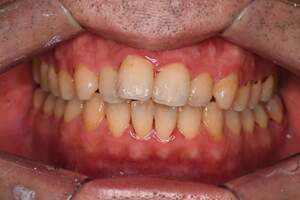

歯石除去

治療前

治療後

| 年齢 | 25歳・男性 |

| 主訴 | 歯石をとりたい・検診 |

| 治療内容 | 各種検査・歯石除去 |

| 治療期間 | 60分 |

| 費用 | 初診料3,000〜4,000円前後 +歯石除去約1,000円 |

| リスク・副作用 | ・処置後に歯がしみることがあります。 ・歯と歯の間に隙間ができるので、息が漏れ発音しにくいと感じることがあります。 ・歯ぐきの炎症が軽減すると歯ぐきが引き締まり、歯が長く見えることがあります。 |

| 担当者所見 | 前歯の裏側にすぐに歯石が溜まってしまいザラザラして気になるとご相談いただいたので適切な歯ブラシの当て方とフロスの通し方をお伝えさせて頂きました。 |